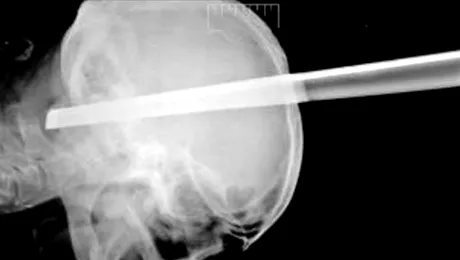

A supraviețuit după ce piciorul unui scaun i-a străpuns craniul